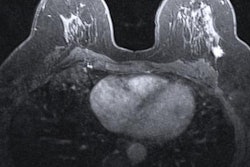

Double reading of mammography screening exams -- and using a third reader or a consensus process to resolve any interpretation discrepancies -- increases the number of cancers detected and reduces recalls, according to a study published online April 10 in Radiology.

To investigate the effect of a double-reading protocol on recall and cancer detection rates, Taylor-Phillips and colleagues used a year's worth of data from 805,206 women culled from 33 breast screening centers in England. Two readers reviewed each mammogram and were aware of whether they were the first or second reader.

Overall, a total of 7,055 cancers were detected, with a mean pathologic size of 16.5 mm. Of these, 77.3% were invasive. Most of the invasive cancers were grade 2 (54.3%) and axillary node negative (76.7%). DCIS alone was identified in 22.7% of cancers; most of these were high grade (63.1%).

Second readers identified an additional 627 cancers that first readers did not. Compared with the cancers identified by first readers, these additional cancers were less likely to be invasive, and if they were invasive, they tended to be lower grade. The additional cancers were also smaller, and if they were DCIS, they were likely to be lower grade. As for recalls, after arbitration, the rate was 4.08%, while the rate for first readers was 4.76%. If there had been no arbitration and women had been recalled if either reader recommended it, the recall rate would have been 6.19%, the authors wrote.